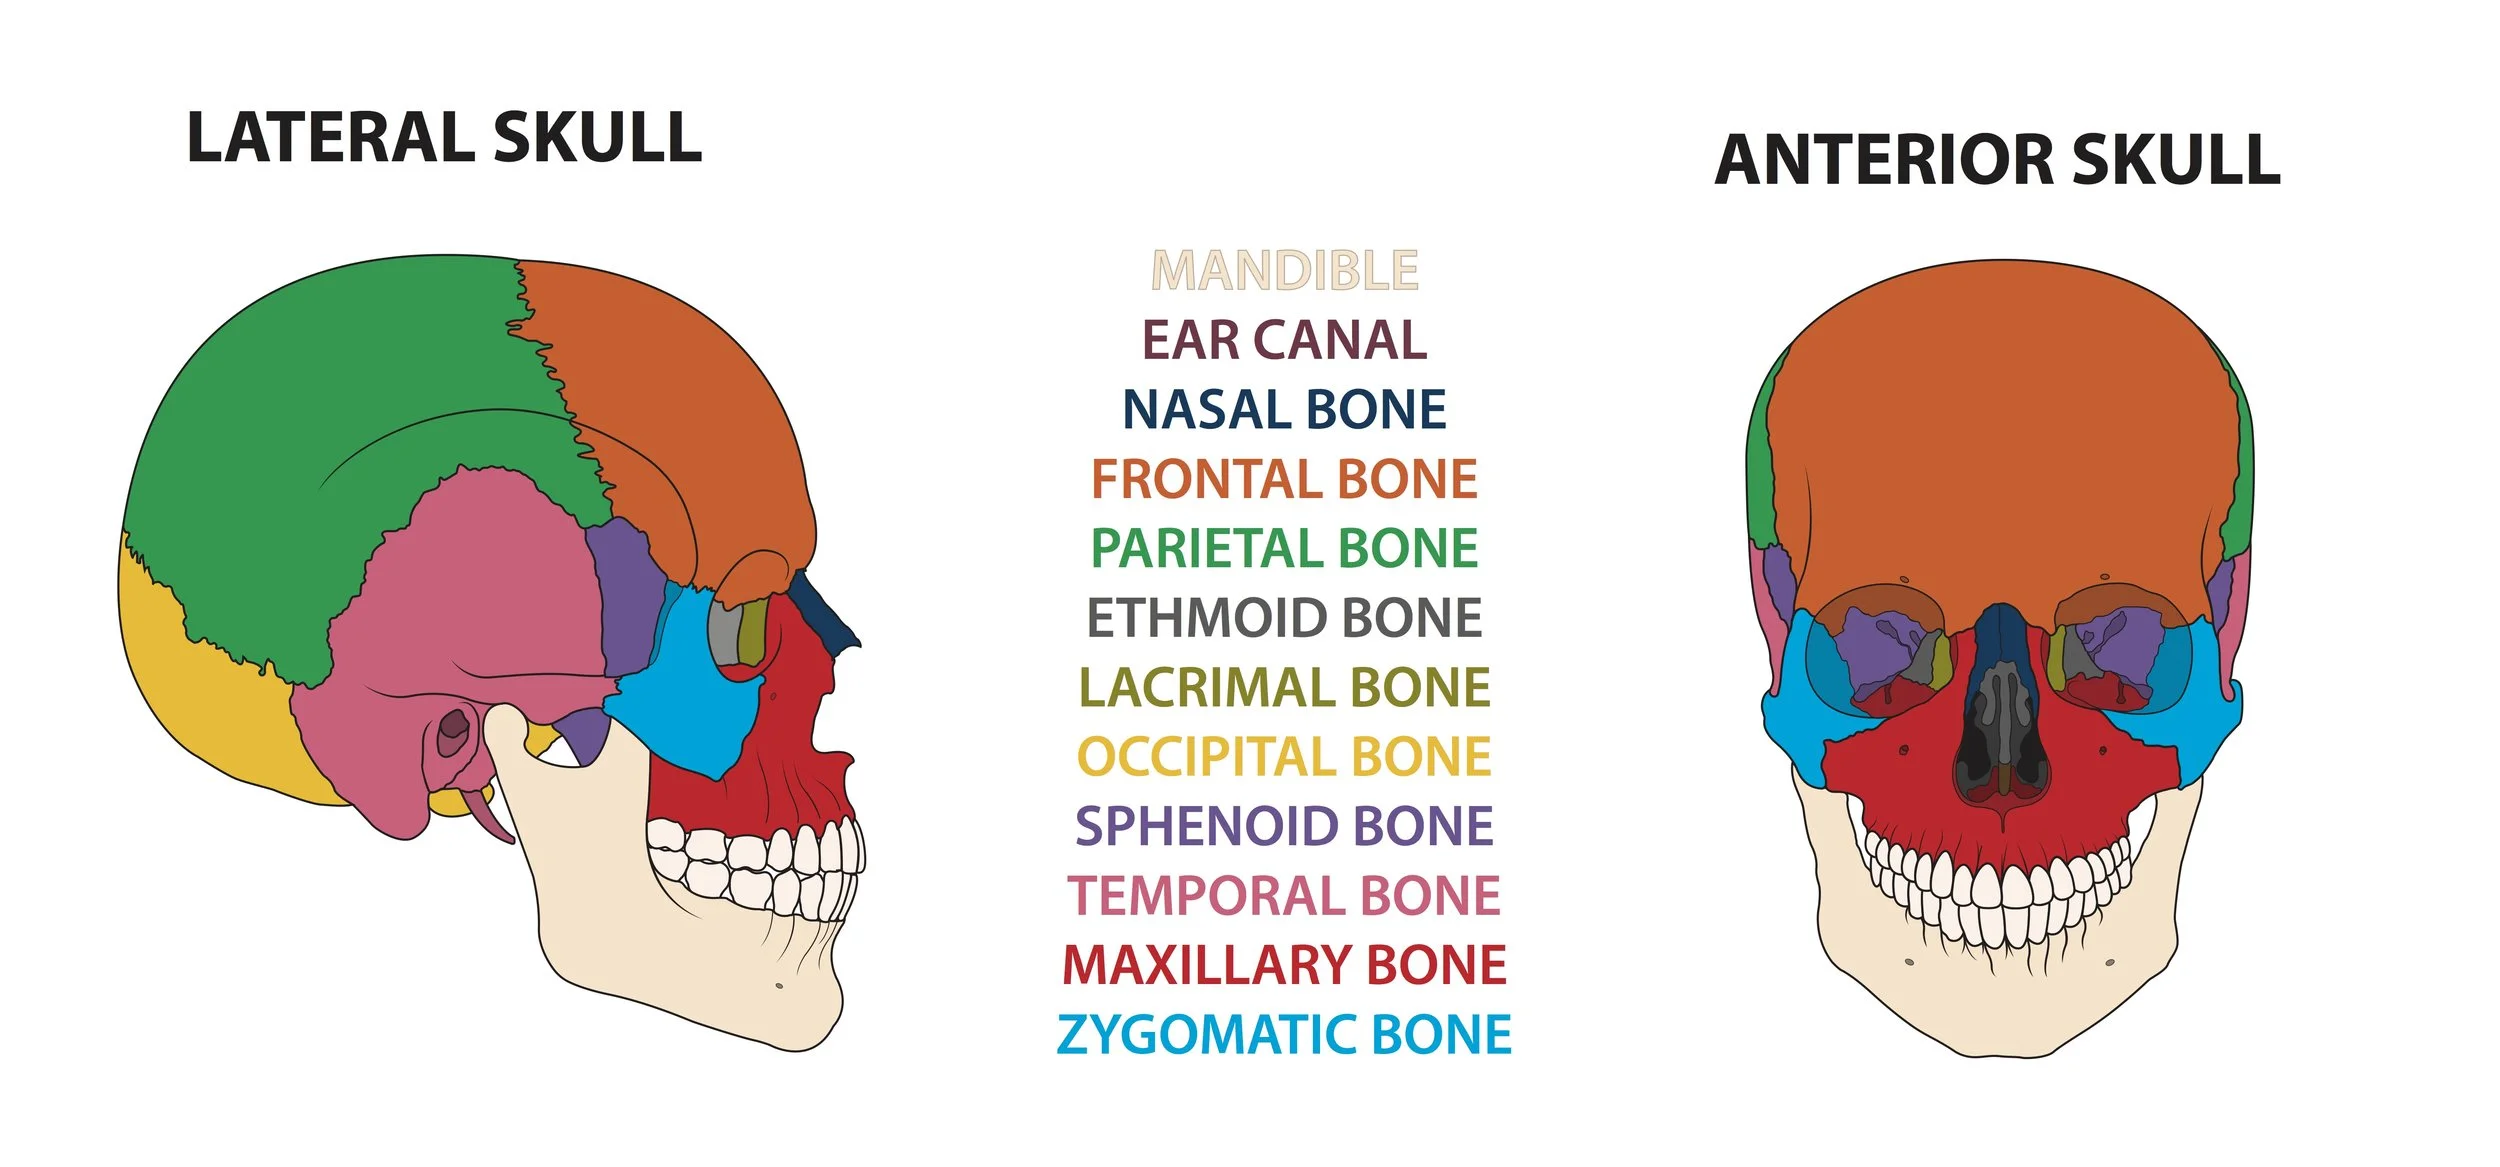

Biomedical art is a form of biological illustration that helps record and disseminate medical, anatomical, and related knowledge. It translates complex technical medical information into visual artwork to support research, patient care and education, public relations, and marketing objectives.